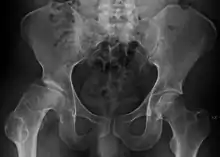

| Radiograph of a person with Legg–Calvé–Perthes disease | |

X-rays of the hip may suggest and/or verify the diagnosis. X-rays usually demonstrate a flattened, and later fragmented, femoral head. A bone scan or MRI may be useful in making the diagnosis in those cases where X-rays are inconclusive. Usually, plain radiographic changes are delayed six weeks or more from clinical onset, so bone scintigraphy and MRI are done for early diagnosis. MRI results are more accurate, i.e. 97–99% against 88–93% in plain radiography. If MRI or bone scans are necessary, a positive diagnosis relies upon patchy areas of vascularity to the capital femoral epiphysis (the developing femoral head).